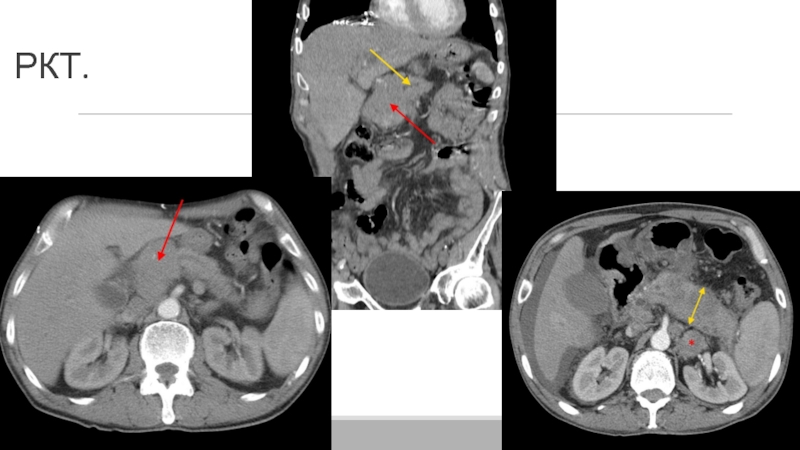

Слайд 36Клинический случай.

Пациентка Н. 59 лет. Отметила у себя пожелтение кожных

покровов. По данным обследования по м/ж , включающие УЗИ, РКТ

органов грудной и брюшной полости, МРТ органов БП, ЭГДС, свидетельствует о раке головки поджелудочной железы, осложненном синдромом механической желтухи.

В этом же месяце больной была выполнена холецистэктомия, наружное дренирование общего печеночного протока(через культю пузырного протока), дренирование брюшной полости в подпеченочной области. Желтуха купирована.

В дальнейшем произошла миграция холангиостомы, образовался наружный желчный свищ. Желчеистечение наружу осуществляется по мигрировавшей холангиостоме, дренажу из подпеченочного пространства.

Клинический случай.Пациентка Н. 59 лет. Отметила у себя пожелтение кожных покровов. По данным обследования по м/ж ,

Слайд 38Клинический случай.

Инструментальные данные:

МРТ органов БП: в головке поджелудочной железы определяется

опухолевое образование размером 3,5х3,5 см. Опухоль сливается со стенкой подковы

двенадцатиперстной кишки, не исключено ее вовлечение. Опухолевый инфильтрат распространяется в чревно- брыжеечный промежуток, на одном из срезов имеется тесное прилежание опухоли к задней полуокружности ВБВ. ВБА представляется интактной.

Тело и хвост поджелудочной железы дистрофичны, панкреатический проток расширен до 0,5 см(норма: до 2 мм), «обрывается» на уровне опухоли.

В парапанкреатической клетчатке( на уровне опухоли) имеются л/у 0,5-0,9 см, сливающиеся с самой измененной головкой.

Клинический случай.Инструментальные данные:МРТ органов БП: в головке поджелудочной железы определяется опухолевое образование размером 3,5х3,5 см. Опухоль сливается

Слайд 40Клинический случай.

Принято решение о хирургическом лечении.

Выполнена гастропанкреатодуоденальная резекция, циркулярная резекция

ВБВ и ВВ с формированием сосудистого соустья протезом Гортекс, резекция

подвздошной кишки с формированием анастомоза бок в бок.

Лабораторные данные на момент выписки:

-биохимическое исследование крови: АЛТ-17 Ед/л( норма:4-40)

АСТ-25 Ед/л(норма: 4-37)

Щелочная фосфатаза- 249 Ед/л(норма: 90-250)

Клинический случай.Принято решение о хирургическом лечении.Выполнена гастропанкреатодуоденальная резекция, циркулярная резекция ВБВ и ВВ с формированием сосудистого соустья